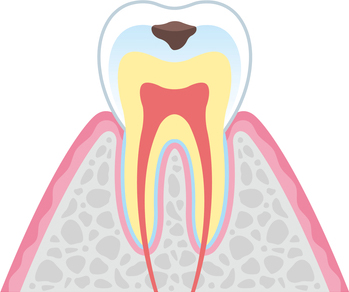

虫歯の進行段階

- C1

エナメル質の虫歯

歯の表面のエナメル質が溶かされ、虫歯が少しずつ進行している状態です。虫歯を正確に削り取り、詰め物をするケースがほとんどです。削らずに定期的なチェックを行うこともあります。

- C2

象牙質の虫歯

エナメル質の奥の象牙質にまで細菌が進行している状態です。象牙質は神経に近いため、知覚過敏として歯がしみるようになります。虫歯を削り取り、詰め物や被せ物をするのが基本です。

- C3

神経まで侵された虫歯

歯の神経が虫歯菌に感染し、強烈な痛みを引き起こします。細菌に感染した組織を除去・清掃・殺菌し、被せ物を被せていきます。

- C4

歯の根まで達した虫歯

歯の大部分が失われている状態です。根の先端に膿が溜まっていると、顎の骨や周囲の歯に悪影響を及ぼすようになり非常に危険です。多くのケースで抜歯を検討します。